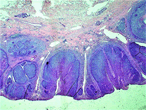

Synchronous non-collision melanoma and basal cell carcinoma arising from chronic lymphedema: a case report and review of literature

Sahned Jaafar and others

Journal of Surgical Case Reports, Volume 2019, Issue 4, April 2019, rjz105, https://doi.org/10.1093/jscr/rjz105